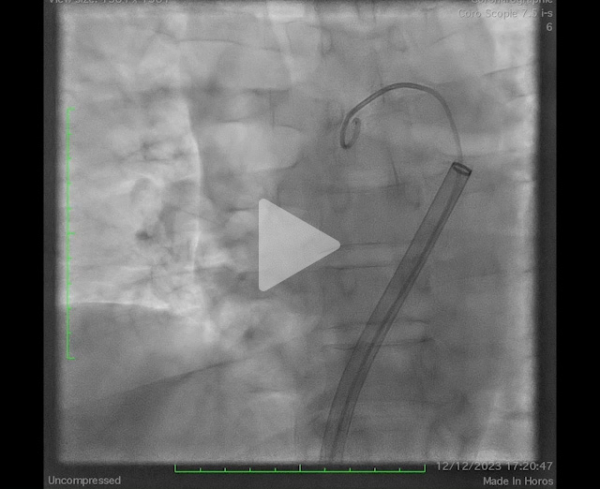

Après discussion collégiale, devant la sévérité du tableau initial et l’absence d’amélioration malgré 24h de traitement anticoagulant bien conduit, il est proposé la réalisation d’une thrombectomie percutanée (dispositif Flowtriever).

Il s’agit d’une procédure réalisable sous anesthésie locale, par voie fémorale écho-guidée (introducteur de grand diamètre – 24F) et sous monitoring de l’efficacité de l’héparinothérapie. Une cathétérisation sélective des 2 branches de l’artère pulmonaire est réalisée permettant la confirmation d’une hypertension pulmonaire initiale (mesurée à ici à 67mmHg pour la PAPs) (Figure 8), la mise en place d’un cathéter dédié de thromboaspiration permettant de ramener le thrombus (Vidéos 2, 3 et 4). À visée d’épargne sanguine, chaque aspiration est filtrée pour permettre une réinjection du sang.

Figure 8 : évaluation initiale des PAPS

Vidéo 2 : angiographie initiale